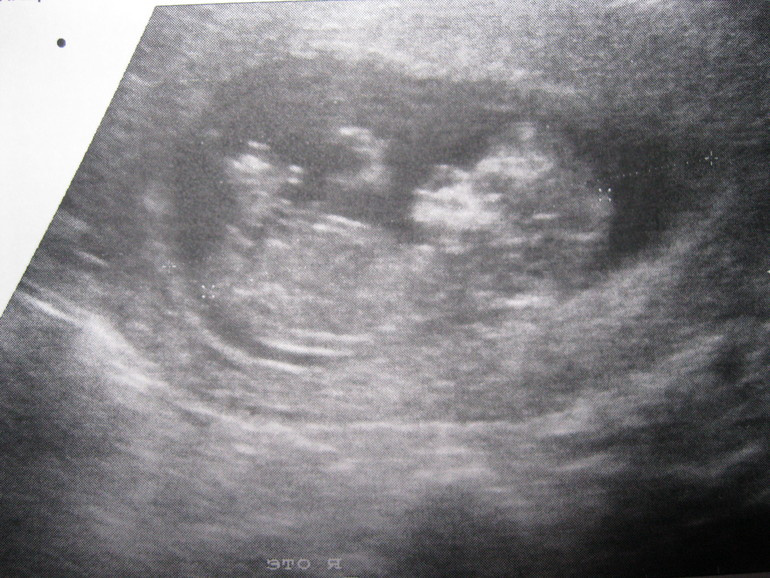

УЗИ, КТГ, доплерСегодня мы прошли Узи+кровь на 1 скрининг. Вроде бы по узи всё хорошо (хотя, я в нормах плохо разбираюсь. Я так понимаю, это нормальные показатели? Под кат.

КТР - 57 мм

Носовая кость - 2,1 мм

ТВП - 1,2 мм

(Срок поставили 12,2 нед.)

И, напоследок, фотка моей ляли))